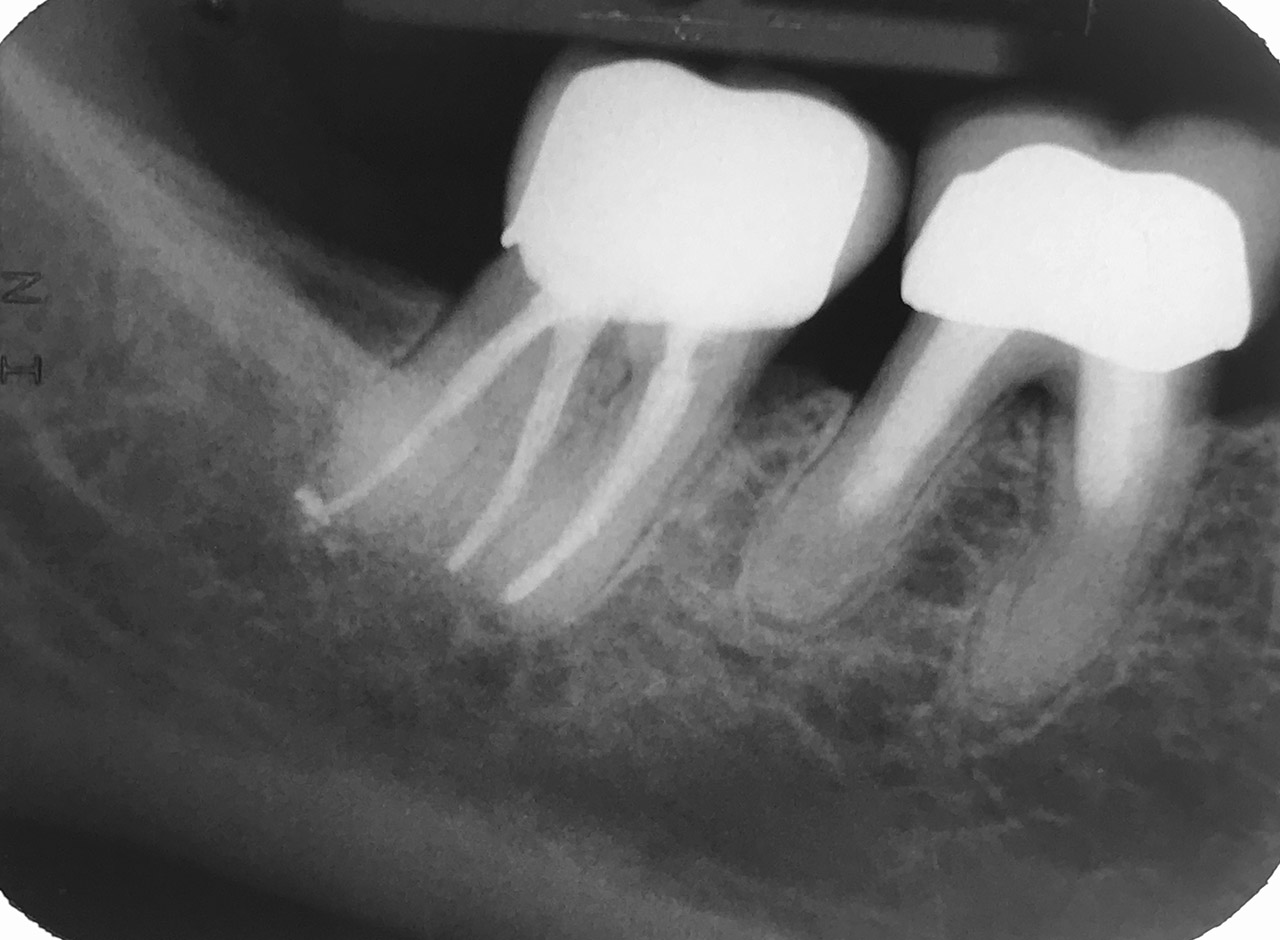

Wurzelbehandlung/Endodontie:

Massiver Paro-/Endodefekt bei den Zähnen 38&37. Extraktion von 38 (Weisheitszahn) und Wurzelbehandlung von 37 (4 Kanäle). Defekt vollständig ausgeheilt.